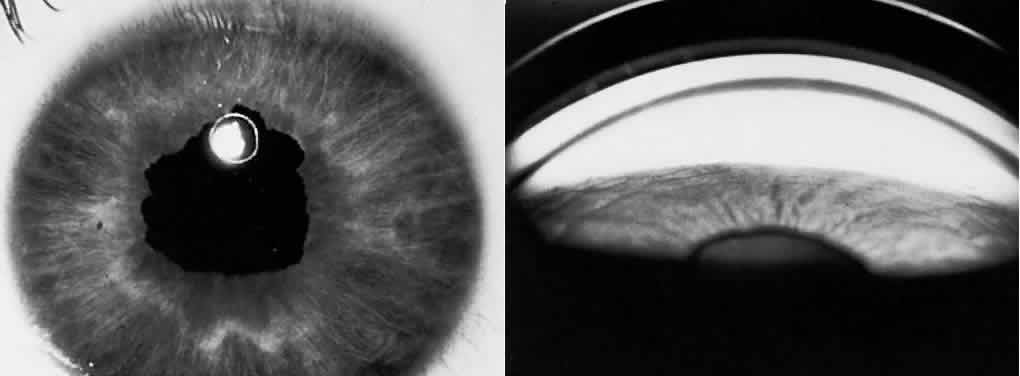

Iris sphincter ischemia during the period of acute IOP elevation compounds the attack by fixing the pupil in the mid-dilated position and may render it unresponsive to topical miotics given to break the attack. Later, secondary dilator and sphincter muscle atrophy may result in an irregular pupil. This muscular atrophy or iris necrosis can be demonstrated histologically (Fig. 6). Glaukomflecken are anterior subcapsular, tiny gray-white lens opacities on slit-lamp examination after acute angle-closure glaucoma (see Fig. 6).63 They probably result from interference with lens epithelial cell metabolism, either as a direct pressure effect or through alterations in the normal constituents of the aqueous during the angle-closure attack. Histologically, small areas of epithelial cell necrosis are seen accompanied by tiny areas of adjacent subcapsular cortical degeneration.

Fig. 6. A. After an acute attack of angle-closure glaucoma, the iris is necrotic. The clinical triad comprises irregular pupil, segmental iris atrophy (the iris from only the 5- to 9-o'clock positions is relatively normal), and glaukomflecken, tiny white anterior subcapsular lens opacities (inset). B. In this area, there is near-total iris necrosis (hematoxylin-eosin, × 10).

The syndrome is characterized by depigmentation of iris pigment epithelium, producing characteristic iris transillumination, which is demonstrable on slit-lamp examination at the junction of the inner two thirds with the outer one third of the iris (Fig. 11). These areas of depigmentation are accompanied by a band of increased granular iris pigmentation overlying the ring of increased iris transillumination. The finding is most easily seen in blue irises but may be seen fairly easily in brown. This band is presumed to be caused by many pigment-laden macrophages within this area of iris stroma. It has been postulated that the distribution of iris depigmentation corresponds to areas where bundles of zonules chafe the iris pigment epithelium. Iridodonesis may be present. Gonioscopic examination reveals that the trabecular meshwork is heavily pigmented. An increased incidence of retinal detachment is also found in PDS, suggesting the possibility of an underlying pigment epithelial defect.

Fig. 11. Pigment dispersion syndrome. (A) Extensive increased iris transillumination is present mainly in the middle third of the iris. (B) Goniscopic view shows marked deposition of pigment in the anterior chamber angle. (C) Melanin pigment granules present in the corneal endothelial cytoplasm are responsible for the Krukenberg's spindle seen clinically (inset). (A, clinical; B, gonioscopy; C, 1.5-μ section, PD, × 300; inset, clinical)

Another typical slit-lamp finding in PDS is the presence of a Krukenberg's spindle, a vertically oriented column of pigment phagocytosed by central and inferior corneal endothelium (see Fig. 11). Pigment may be found within the aqueous after pupillary dilatation or after exercise. Such pigment release may be accompanied by an acute rise in IOP. Significant deposits of pigment also are found on the iris surface, lens, and zonules and within the trabecular meshwork.

Histologically, the posterior layer of iris pigment epithelium atrophies in areas that correspond to the foci of iris transillumination.315 The dilator muscle may be atrophic, hypertrophic, or absent. The adjacent iris stroma contains large numbers of pigment-filled macrophages. Neuroepithelial melanin granules are widely distributed within the endothelium of the cornea (corresponding to the Krukenberg's spindle) (see Fig. 11) and within the trabecular meshwork; however, endothelial cell counts have been reported to be similar to those in control patients.316,317